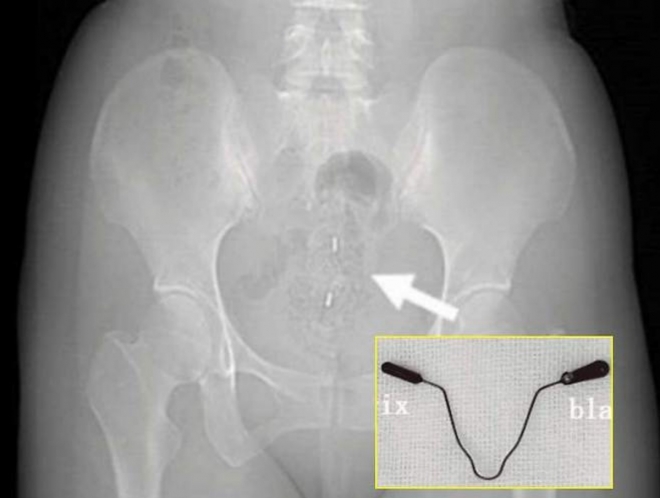

검사 결과 환자의 몸에서는 2년 전 삽입한 피임 장치가 자궁을 관통해 방광 후벽을 파고든 상태였다.

피임 기구가 자궁을 뚫고 방광까지 침투한 사례. 큐레우스 제공

의학 저널에 소개된 여성 환자는 의료진의 권유에 따라 방광을 절개해 자궁 내 장치를 제거하고 손상된 방광벽을 봉합하는 치료를 받았다. 또 수술 후 요도 카테터를 14일간 유지한 뒤 제거했다. 이후 자궁과 난소, 배뇨 기능 모두 정상을 회복했다.